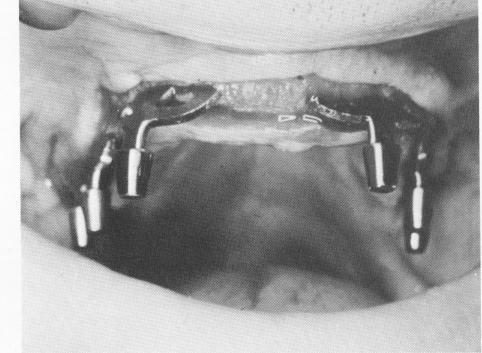

Fig. 11-199. Nearly perfect parallelism can be achieved easily with the blade. The necks are bent outside the mouth, then the blades are replaced in their grooves.

1 Nearly perfect parallelism achieved easily with dental blade implants